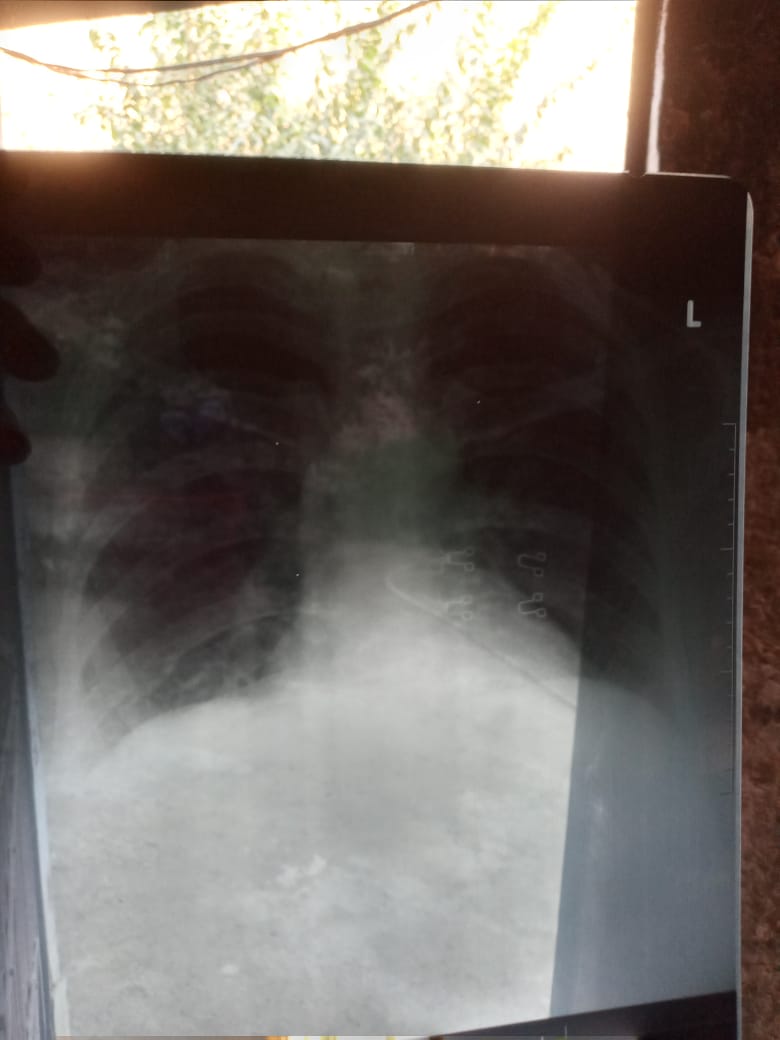

Pt has fever for 3 days of 101-102° relieved by panadol. Loss of sense of taste. X ray of chest shows chest attaching the prescription and all reports, please tell of the prescription is correct and pt has covid-19?

ur x ray is not clear . labs should from authentic lab .

Due to pendamic HRCT would be much better and clear the results.. Set an appointment for medicine related problems.